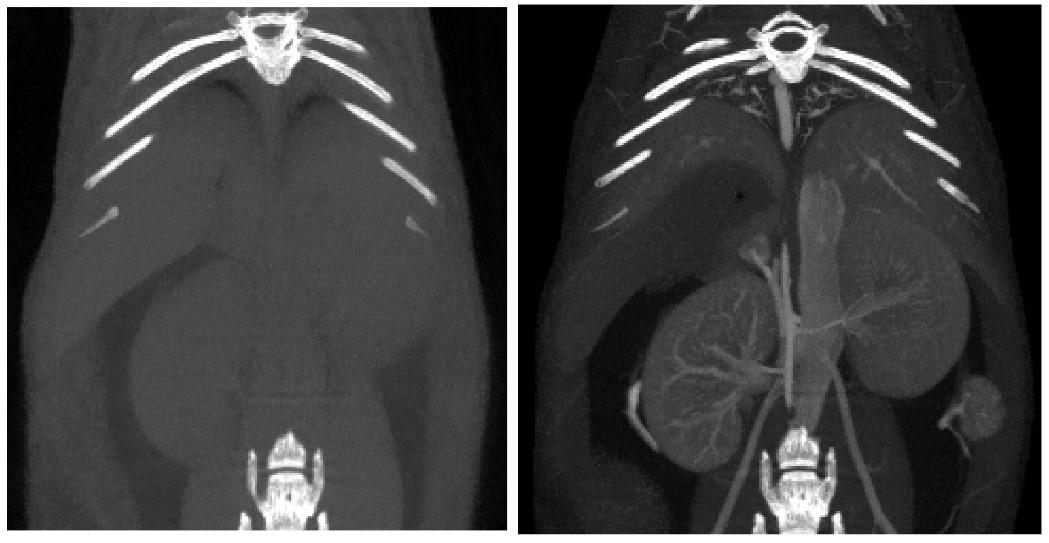

Contrast-enhanced CT:

對比增強(qiáng)CT.jpg

6、Contrast-enhanced tumor CT imaging

Tumor study: Contra-enhanced CT was used to examine liver tumors in living mice: Exitron 12000 was injected, FDK was reconstructed, and the imaging time was 4min, 100μm voxel size.